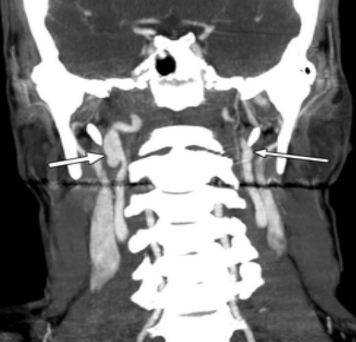

Коронарное изображение МСКТ демонстрирует саккулярный затек контраста (толстая стрелка) из правой внутренней сонной артерии (псевдоаневризма). Левая сонная артерия (тонкая стрелка) не повреждена.